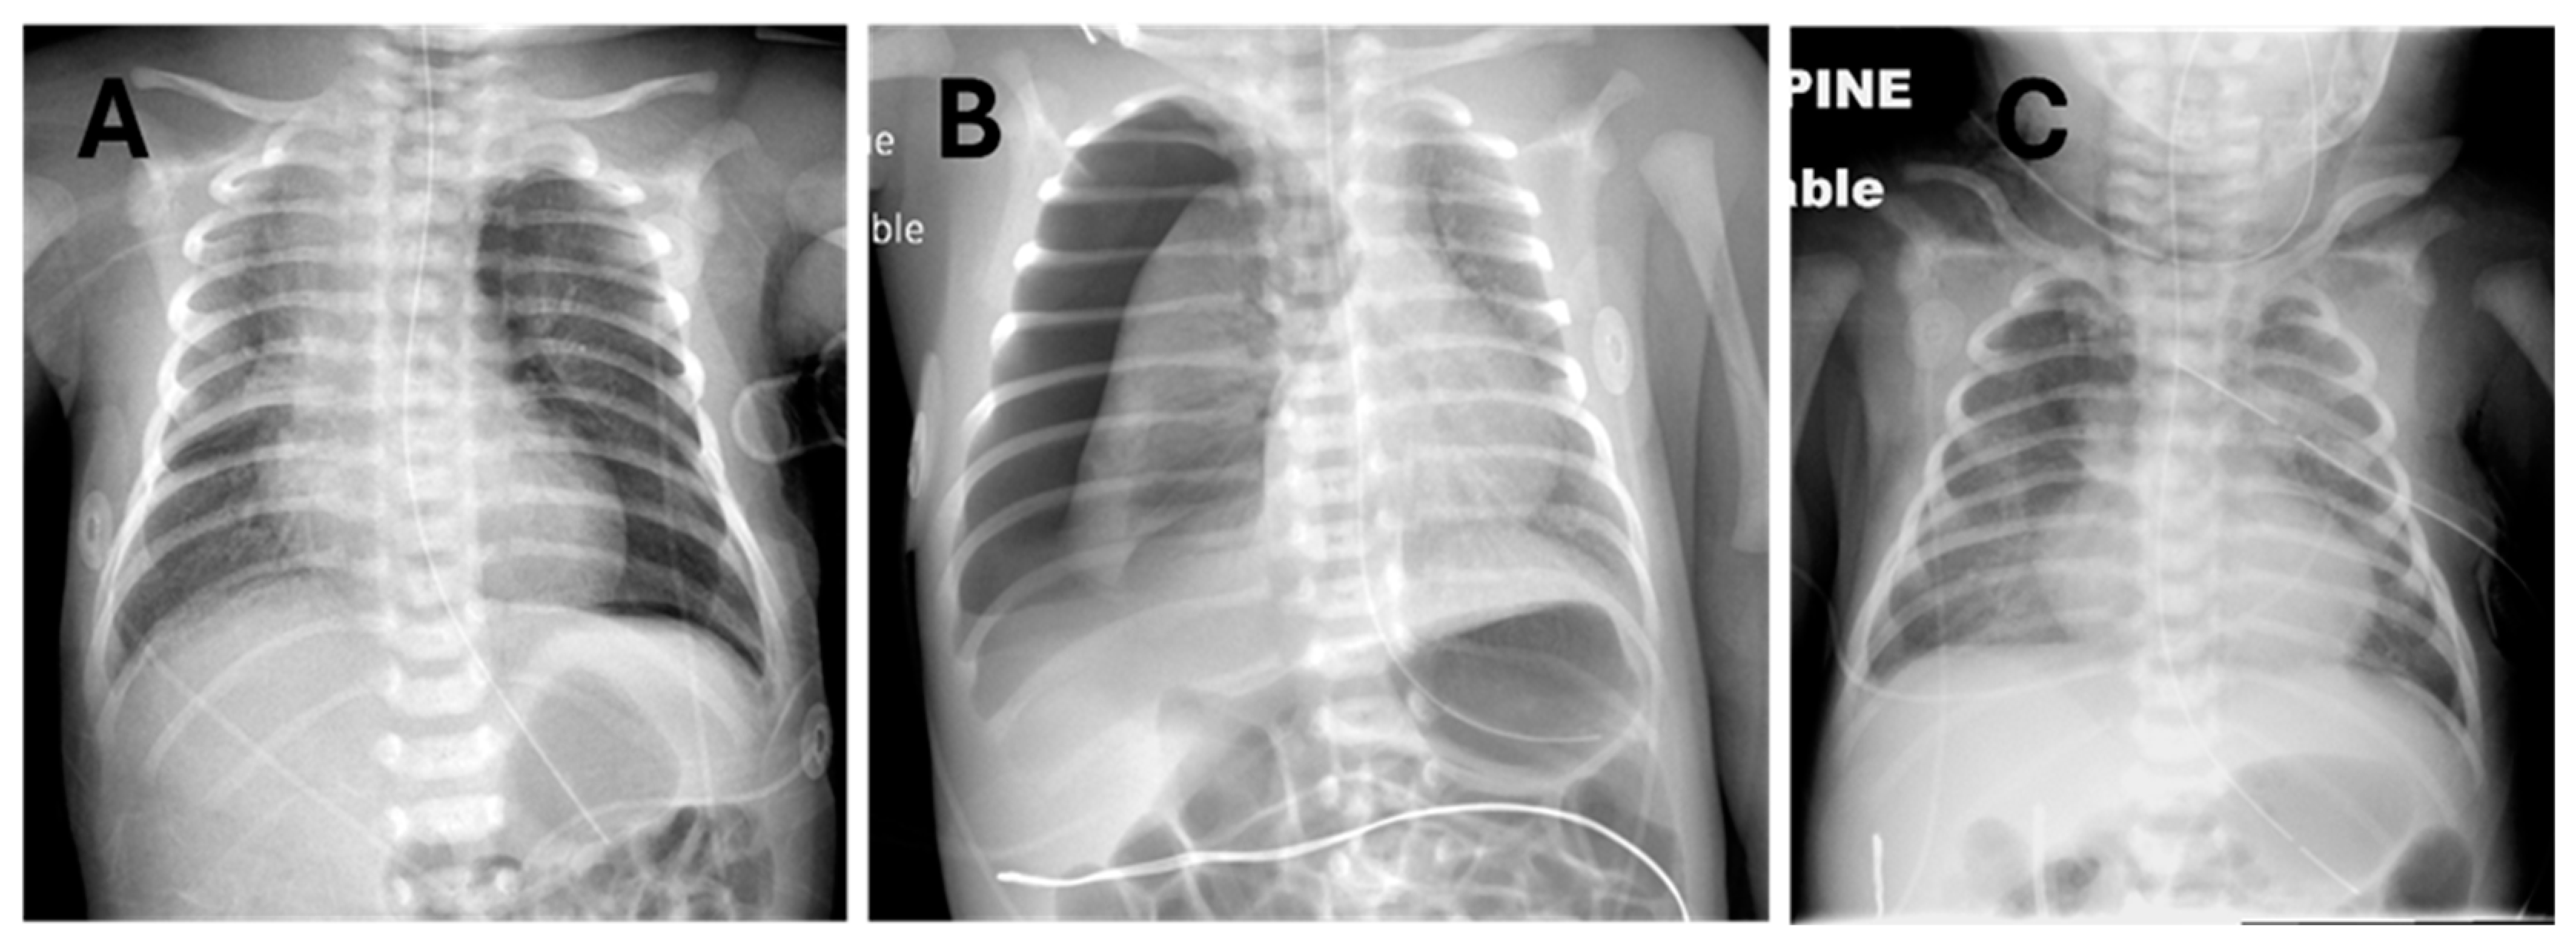

The clinical decision on how to administer surfactant to neonates with RDS and PTX was made by the attending neonatologist, considering the individual circumstances of each patient. Briefly, it must first be decided whether or not to evacuate the pneumothorax to minimize cardiorespiratory dysfunction and optimize lung inflation to prevent maldistribution of surfactant. Examples where non-evacuation and evacuation were chosen are shown in Figure 1, panels A and B, respectively. Figure 1C exemplifies a neonate who had severe pneumothoraces and pneumomediastinum, a prior dose of surfactant, and successful evacuation of most of the pleural air with thoracentesis and a chest tube but who still had an active air leak and significant oxygen requirement yet had never been mechanically ventilated. In most instances where thoracentesis is performed, the adequacy of the procedure is assessed clinically based on the volume of gas aspirated, transillumination when feasible [14], auscultation, and acute increase in O2 saturations by pulse oximetry; surfactant administration is usually performed immediately after thoracentesis, without repeating a chest X-ray.

Figure 1. Prototypical examples of pneumothorax on chest radiographs before surfactant administration via LMA. (A) Left pneumothorax not drained. (B) Right pneumothorax prior to thoracentesis. (C) Left pneumothorax after chest tube drainage with residual bilateral pneumothorax and pneumomediastinum plus emphysema in the neck tissue planes.